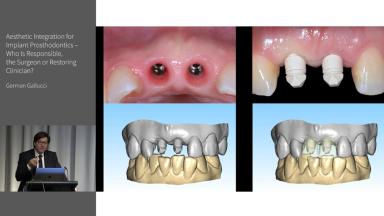

In his lecture, Dr. Gallucci addresses the critical role of interdisciplinary collaboration in implant dentistry, with a focus on the esthetic zone. He emphasizes the necessity of coordinated efforts between the surgical and restorative teams for successful outcomes in anterior zone implantation. Key topics include the precision of surgical implant placement, the importance of preserving soft tissue and contour, and the seamless transition to the prosthetic phase for effective crown loading. Dr. Gallucci also highlights the indispensability of a pre-operative restorative plan, the use of digitally guided treatment planning, and the alignment of the implant's vertical position with the planned prosthesis.

- explain the importance of collaboration between surgical and restorative teams for successful implant placement in the esthetic zone

- elaborate on the key elements of transitioning from implant placement to the prosthetic phase, ensuring a successful crown loading and esthetic integration

- discuss the shared responsibilities of the surgical and restorative teams and the importance of effective communication for optimal outcomes in implant dentistry